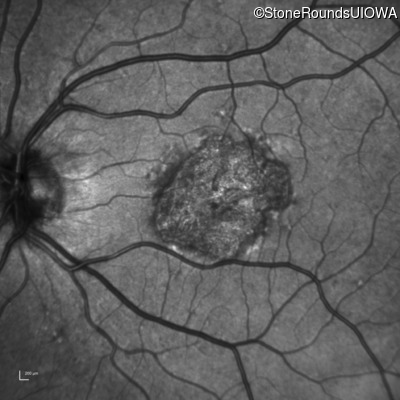

Infrared Fundus Photograph - Right - 20/40 -1

Exemplar